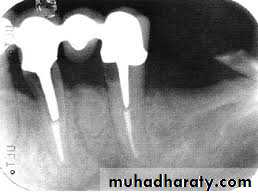

PERSISTENT/SECONDARY ENDODONTIC INFECTIONS

persistent intraradicular infections are caused by microorganisms that resisted intracanal antimicrobial procedures and survived in the treated canal.Involved microorganisms are remnants of a primary or secondary infection. The latter, in turn, is caused by microorganisms

that at some time entered the root canal system secondary to clinical intervention .The moment can be during treatment,

between appointments, or even after root canal filling. In any circumstance, if penetrating microorganisms manage to adapt

themselves to the new environment, surviving and flourishing, a secondary infection is established. Species involved can be

oral microorganisms or not, depending on the source of secondary infection

Bacteria at the Root Obturation Stage

Bacteria persisting in the root canal after chemomechanical procedures or intracanal medication will not always maintainan infectious process. This statement is supported by evidence that some apical periodontitis lesions healed even after bacteria were isolated from the canal at the obturation stage. There are some possible explanations :

♦ Residual bacteria may die after obturation because of toxic effects of the filling material or sealer, access denied to

nutrients, or disruption of bacterial ecology.

♦ Residual bacteria may be present in quantities and virulence subcritical to sustaining periradicular inflammation.

♦ Residual bacteria remain in locations where access to periradicular tissues is denied